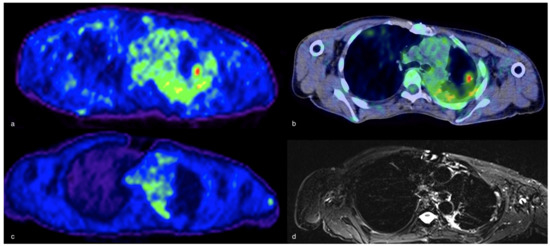

- Thomas, B.A.; Molton, J.S.; Leek, F.; Pang, Y.; Totman, J.J.; Paton, N.I.; Townsend, D.W. A comparison of 18F-FDG PET/MR with PET/CT in pulmonary tuberculosis. Nucl. Med. Commun. 2017, 38, 971–978. [Google Scholar] [CrossRef] [PubMed]